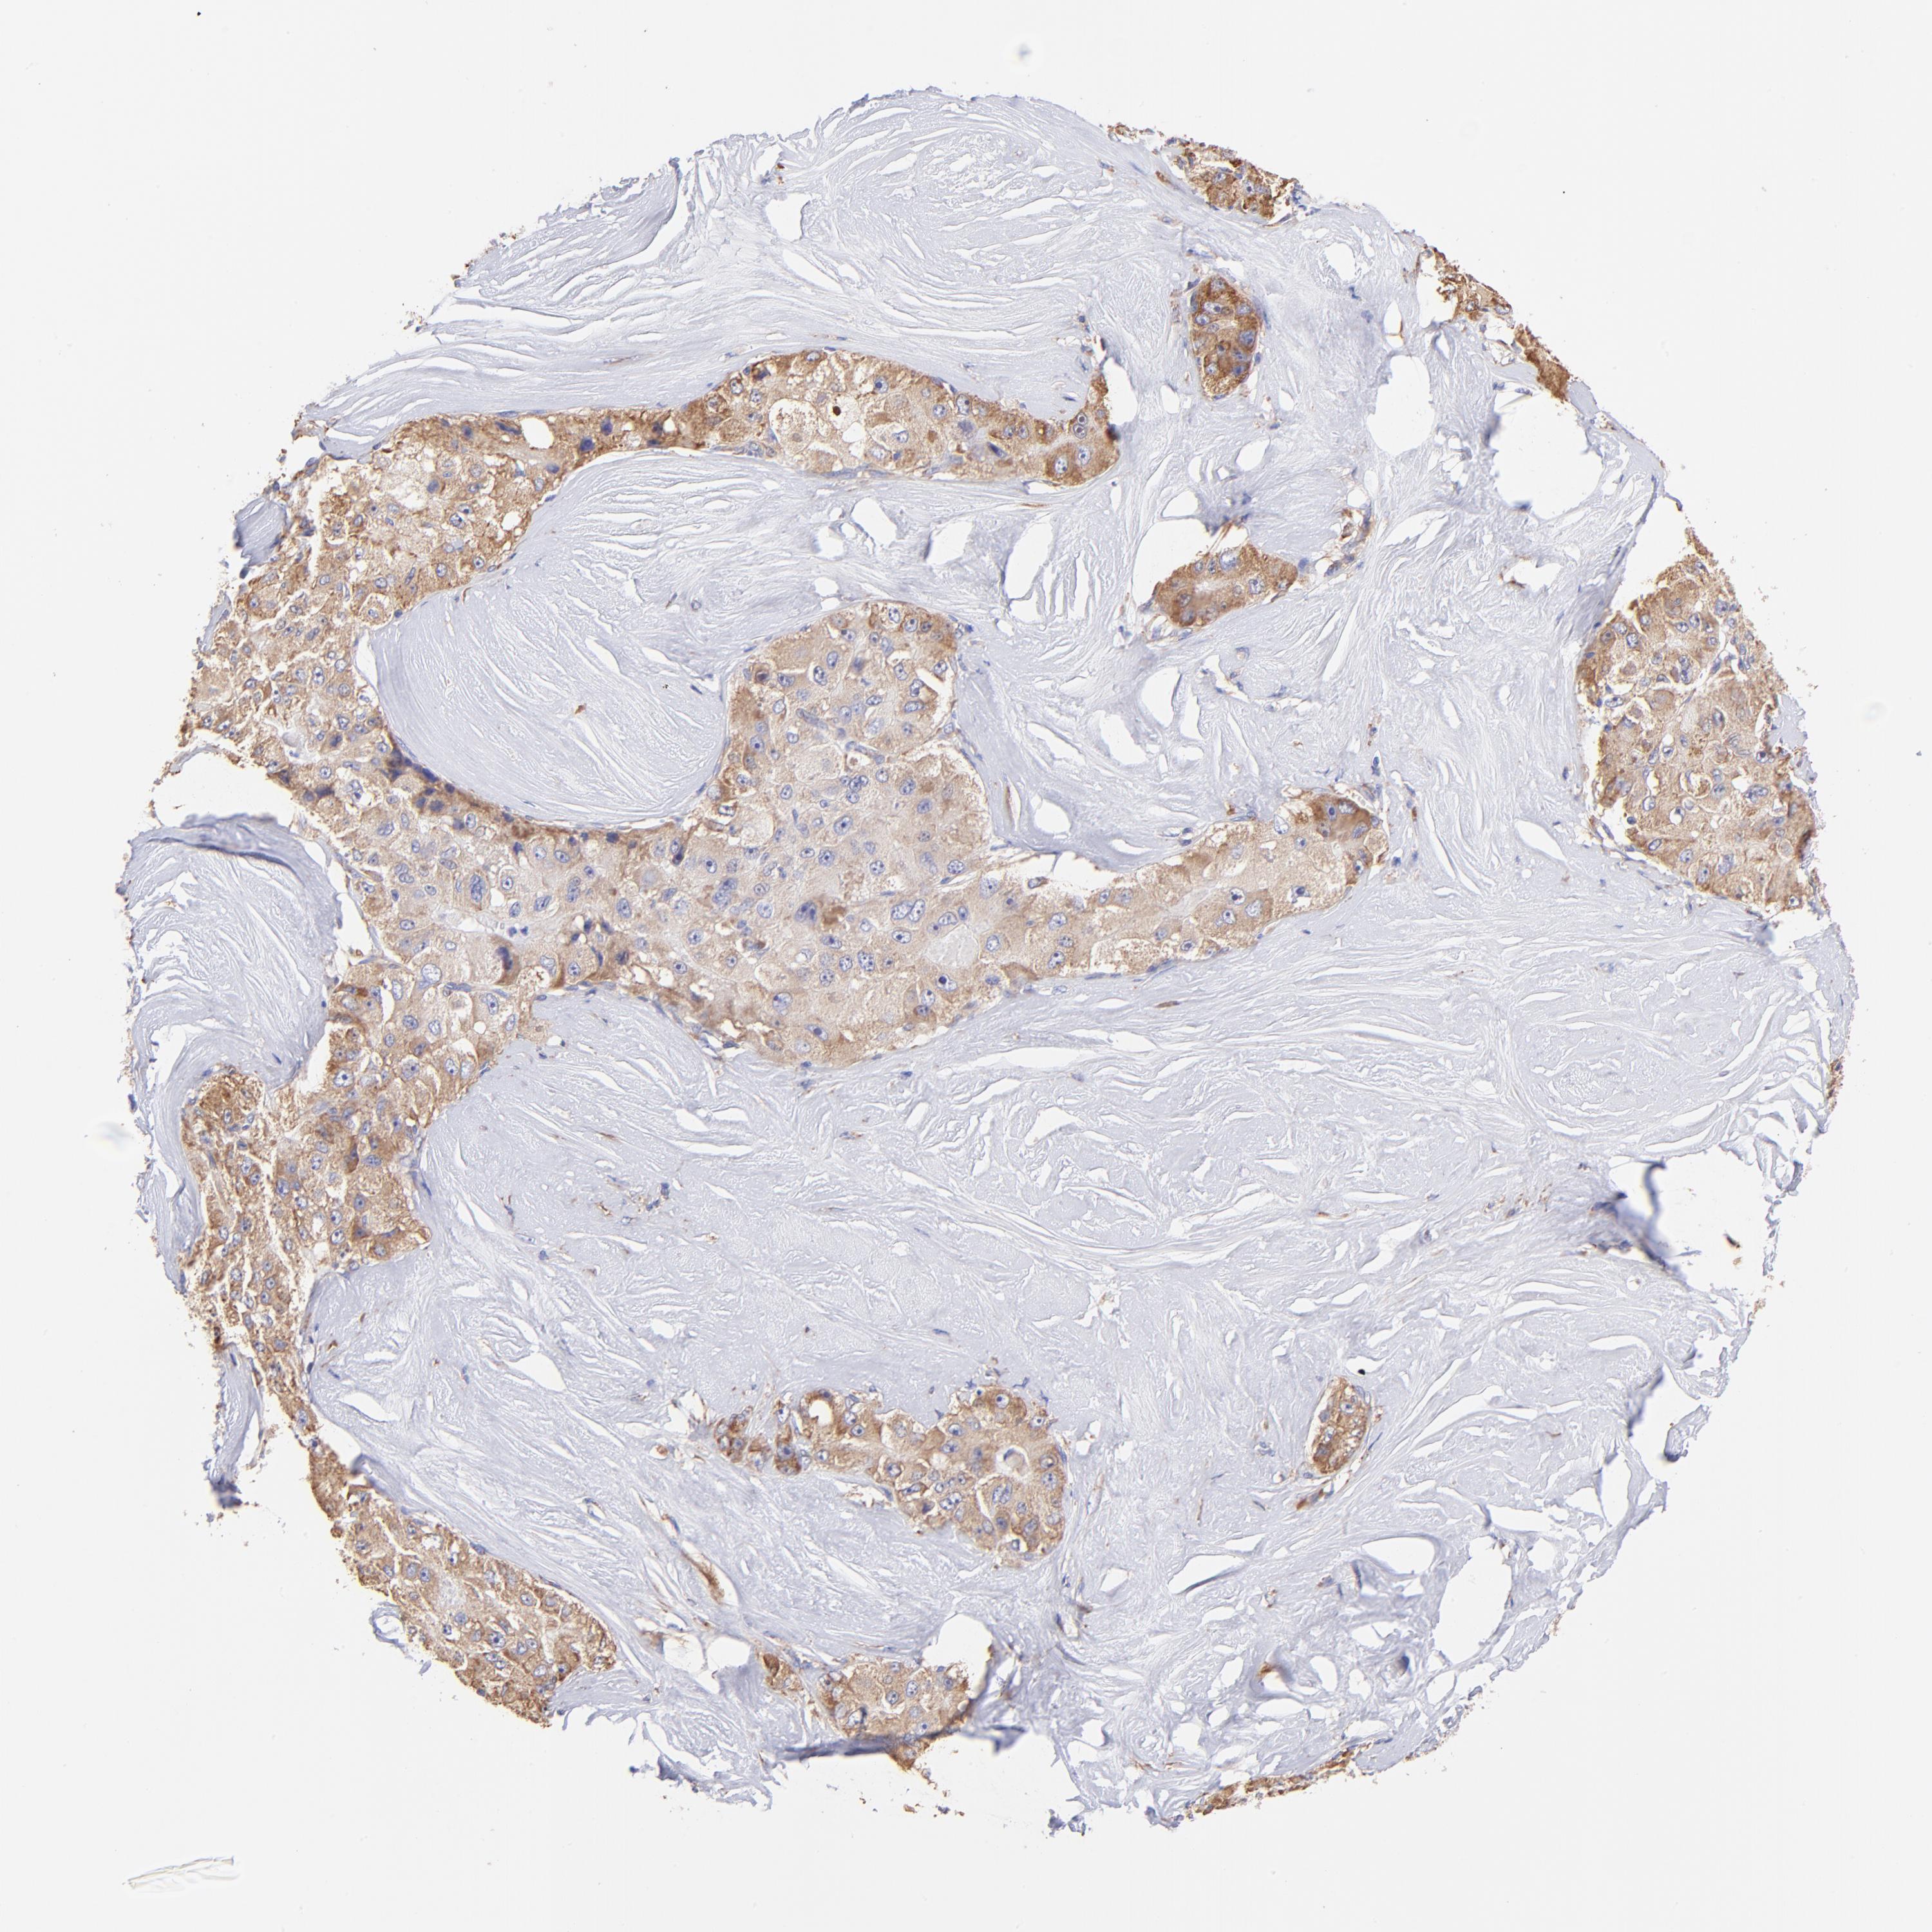

LIVER CANCER - Protein expressioni

A mouse-over function shows sample information and annotation data. Click on an image to view it in a full screen mode. Samples can be filtered based on level of antibody staining by selecting one or several of the following categories: high, medium, low and not detected. The assay and annotation is described here.

Note that samples used for immunohistochemistry by the Human Protein Atlas do not correspond to samples in the TCGA dataset.

Antibody stainingi

Antibody staining in the annotated cell types in the current human tissue is reported as not detected, low, medium, or high, based on conventional immunohistochemistry profiling in selected tissues. This score is based on the combination of the staining intensity and fraction of stained cells.

Each image is clickable and will lead to virtual microscopy that enables deeper exploration of all samples and also displays staining intensity scores, fraction scores and subcellular localization as well as patient and tissue information for each sample.

Antibody HPA002651

Staining

High

Medium

Low

Not detected

Intensity

Strong

Moderate

Weak

Negative

Quantity

>75%

75%-25%

<25%

None

Location

Nuclear

Cytoplasmic/membranous

Cytoplasmic/membranous,nuclear

Cholangiocarcinoma

Carcinoma, Hepatocellular, NOS